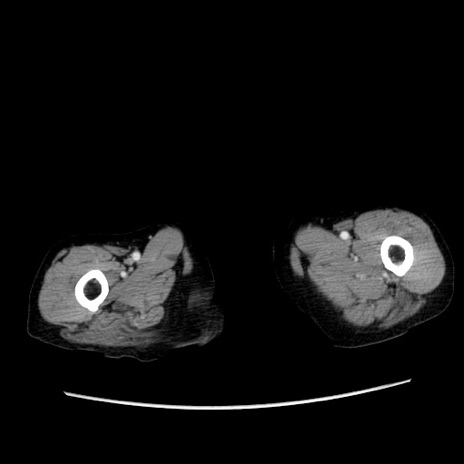

症例25(横断像)

【症例】80歳代女性

【主訴】胸のつかえ感

【現病歴】約9時間前に食後から胸のつかえた感じあり、嘔吐あり、来院。

【既往歴】胃癌(全摘)、胆摘、虫垂炎

【身体所見】心窩部に圧痛あり、反跳痛なし。

【データ】WBC 5700、CRP 0.05